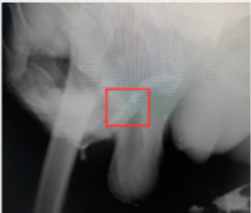

入院后完善尿道造影检查,发现李大爷前尿道狭窄段明显。

遂请成人ai 泌尿外科主任医师王建伟远程会诊,考虑到李大爷尿道狭窄段较长,周围组织粘连严重,用扩张等方式无法最终解决问题,甚至需要做好终身性膀胱造瘘的打算,王建伟主任建议采用口腔黏膜进行修补。